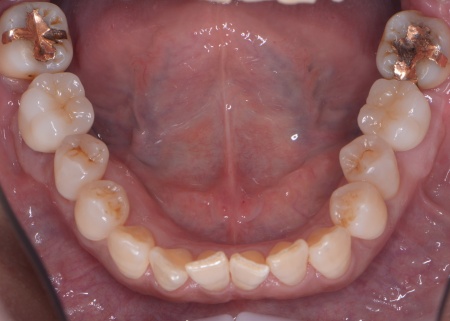

60代女性 重度の歯周病に対して歯周組織再生療法とインプラント治療を施した例

拝見したところ、上下左右の奥歯計8本(第1大臼歯、第2大臼歯)に重度の歯周病が認められました。

特に下の奥歯2本(左右第1大臼歯)は歯を支えている骨が著しく減少して歯が大きく揺れており、治療して温存することは難しい状態でした。

以上のことから、下左右の第1大臼歯は抜歯後に歯を補う治療、その他奥歯の治療、再発した虫歯の治療が必要と診断しました。

下左右の第1大臼歯を抜歯し、その部位にインプラントを埋め込む手術を行いました。同時に、インプラントの隣にある下の第2大臼歯に対して歯周組織再生療法を施しています。